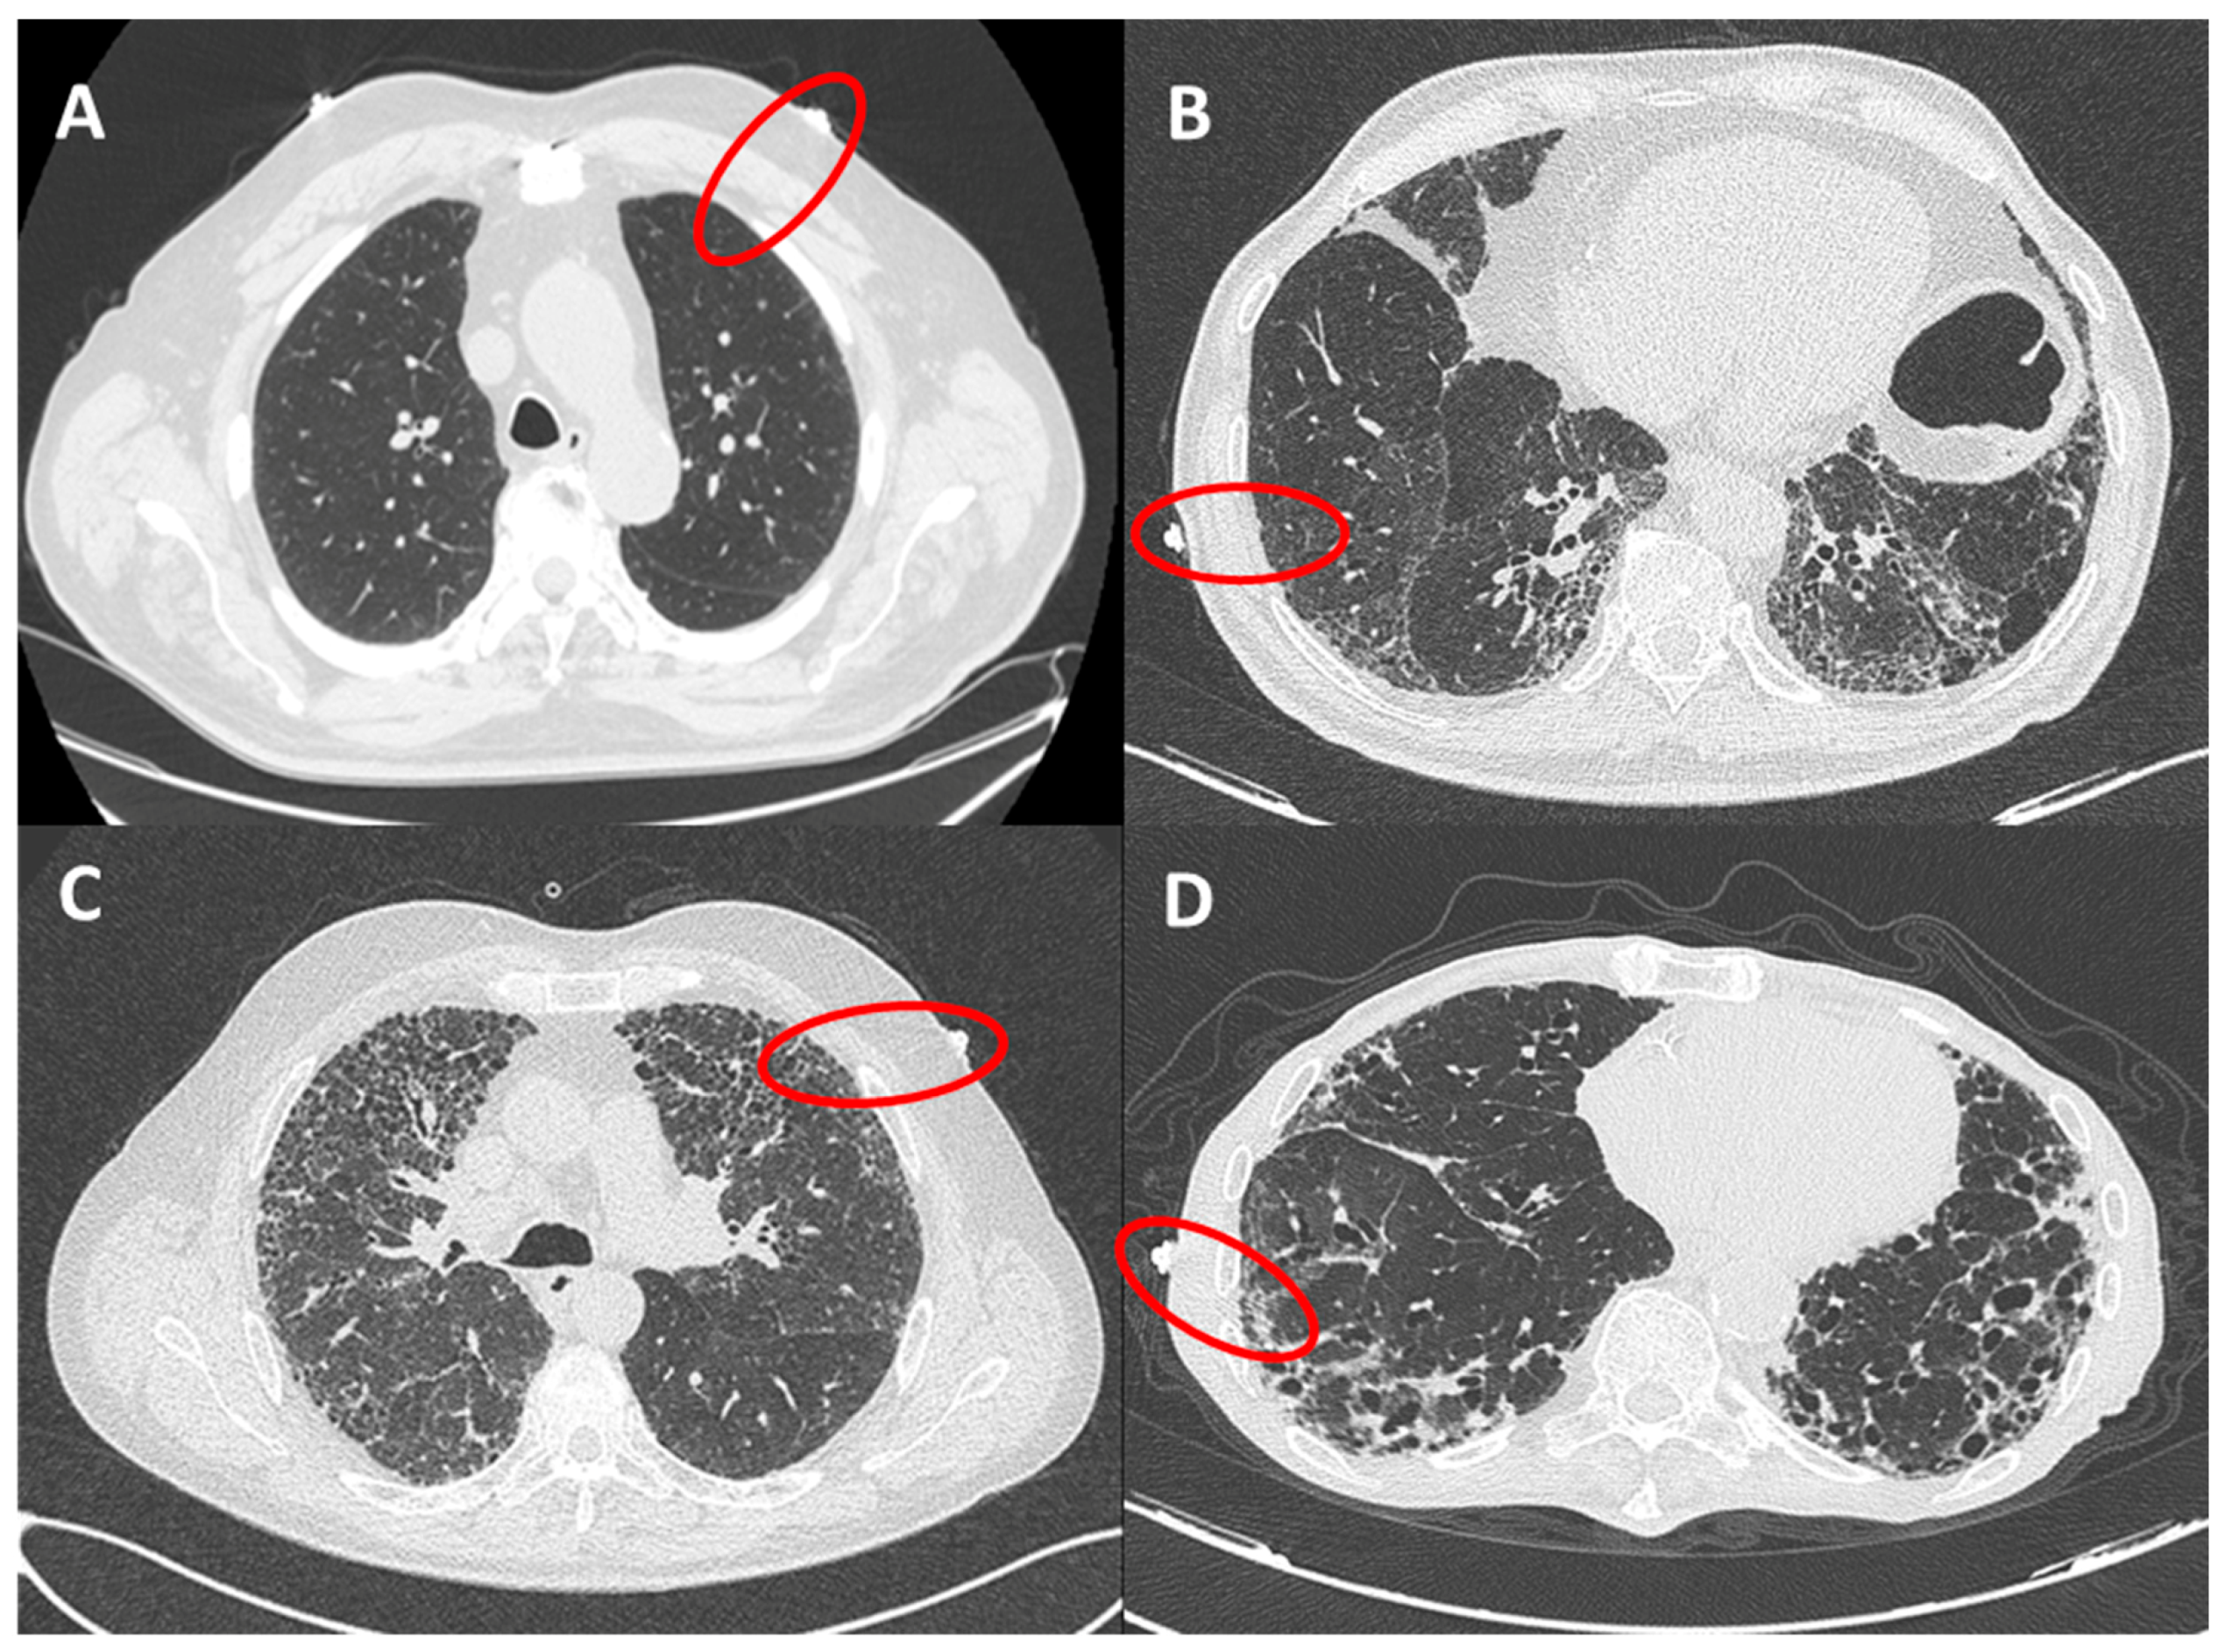

The presence of fibrotic infiltrates on HRCT was evaluated and contemporaneously graded by 2 radiologists (ARL and LC), with expertise in fibrotic interstitial diseases. The analysis was performed only on peripheral lung (within 2 cm in depth from visceral pleura and corresponding to dimension of secondary lobule) and reported as grade 1 (from 0% to 10% of fibrotic changes, mild alterations), grade 2 (10%–50%, moderate), grade 3 (50%–90% severe) and grade 4 (90%–100%, massive fibrotic subversion or honeycomb) (Figure 2). A concordant HRCT score was provided.

Figure 2.

HRCT grades related to red circles showing landmarks of ultrasound assessment. (A): grade 1 (from 0 to 10% of fibrotic changes, mild alterations); (B): grade 2 (10–50%, moderate); (C): grade 3 (50–90% severe); (D): grade 4 (90–100%, massive fibrotic subversion or honeycomb).